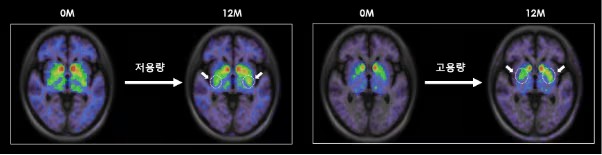

根據(jù)S.Biomedics公司本月初在奧地利維也納舉行的國(guó)際會(huì)議上公布的研究結(jié)果,低劑量和高劑量治療組患者的運(yùn)動(dòng)功能評(píng)分較植入前均提高了高達(dá)28.9%。低劑量和高劑量組患者的精神和情緒癥狀以及自主神經(jīng)癥狀也均得到顯著改善。

尤其是在干細(xì)胞治療帕金森病植入一年后,對(duì)腦成像圖像進(jìn)行分析后發(fā)現(xiàn),多巴胺轉(zhuǎn)運(yùn)蛋白的表達(dá)較植入前有所增加。干細(xì)胞治療的開發(fā)者、延世大學(xué)醫(yī)學(xué)院金東旭教授指出:“這表明干細(xì)胞在腦內(nèi)存活,成熟為多巴胺神經(jīng)細(xì)胞,并與周圍區(qū)域和突觸(神經(jīng)細(xì)胞之間的連接)形成整合?!彼a(bǔ)充道:“這可以被視為帕金森病中替換死亡多巴胺神經(jīng)細(xì)胞的根本治療機(jī)制的有力證據(jù)。”